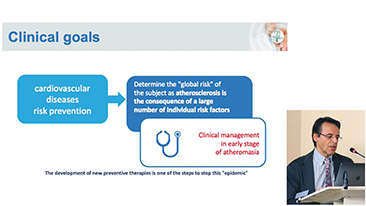

COVID-19: un tiempo desafiante para las personas y los dispositivos

Como consecuencia de la COVID-19, los hospitales y el personal mĂ©dico han desarrollado nuevas prĂĄcticas de trabajo que implican, en los entornos crĂticos, el distanciamiento social, el uso estricto de equipos de protecciĂłn personal (EPP), el lavado de manos y la desinfecciĂłn del equipo todos los dĂas. Los equipos portĂĄtiles altamente mĂłviles y versĂĄtiles pasaron a primer plano en los puntos de atenciĂłn (POC), especialmente cuando las salas y los quirĂłfanos estĂĄn distribuidos en varias plantas y el acceso a los dispositivos especializados es un bien escaso.